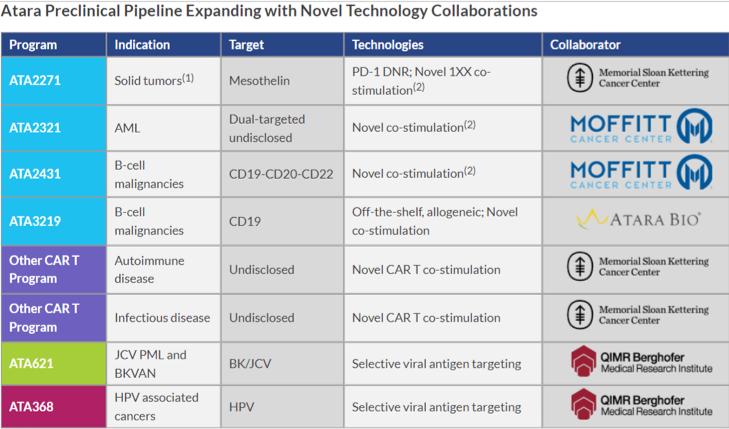

Its lead product candidate for mesothelioma is ATA2271 that uses a novel CAR T 1XX co-stimulation and CAR T PD-1 DNR, which is in preclinical stage. A MSK sponsored Phase 1 study (NCT02414269) of a mesothelin-targeted CAR T immunotherapy is currently under progress with emphasis on development of a next-generation, mesothelin-targeted CAR T using novel 1XX CAR signaling and PD-1 dominant negative receptor (DNR) checkpoint inhibition technologies. The company has exclusive licensed global rights to a mesothelin-targeted chimeric antigen receptor T-cell (CAR T) immunotherapy for solid tumors from Memorial Sloan Kettering Cancer Center (MSK) as per a company press release.

Image Source: https://www.atarabio.com/pipeline/preclinical-programs/

The company has created T-Cells to recognize EBV and CMV Viral antigens and the tumor associated antigen, Wilms tumor 1 (WT1) using technology licensed from MSK and developed product candidates namely ATA129, ATA230, and ATA520. It has a licensing agreement with QIMR Berghofer for the use of its T-Cell technology that can target selective antigen for specific EBV, CMV, HPV, and BK viral antigens and is developing product candidates ATA188, ATA621, ATA368, and ATA274 on the basis of this technology.

The company is fully focused on CAR T opportunities and is developing numerous next generation and off-shelf technology options that cover a gamut of targets and diseases, overcome resistance and have an improved safety profiles. It has collaboration with Moffitt Cancer Centre and MSK to develop multi-targeted CAR T Immunotherapies.

Atara has a strong pipeline of product candidates in clinical development stage such as Tab-cel® (tabelecleucel) for treatment of hematologic and solid tumors, Solid Tumors, Acute Myeloid Lukemia, B-Cell Malignancies, Autoimmune disease and Infectious disesase CAR T programs to name a few.